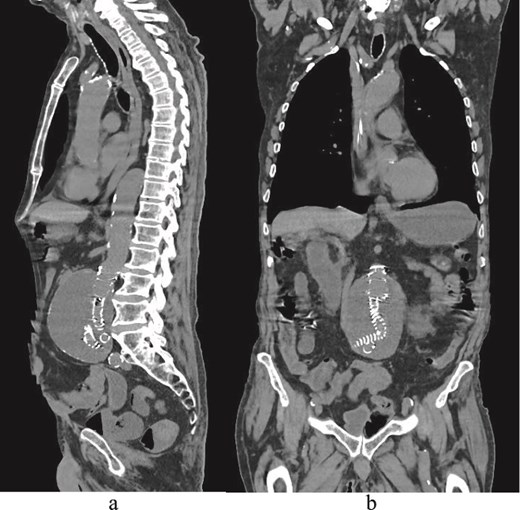

He presented with acute-onset abdominal pain, profuse vomiting, and diarrhea that began 1 day prior to admission. A contrast-enhanced CT scan revealed duodenal obstruction due to extrinsic compression by the aneurysmal sac, now measuring 9 cm in anteroposterior diameter, particularly at the level of the third portion of the duodenum (Figs 1 and 2). There was no evidence of endoleak. Incidentally, the scan also identified a suspicious rectal lesion. Laboratory investigations showed acute-on-chronic kidney injury with significant electrolyte disturbances. Initial management included nasogastric decompression, which yielded 3000 ml of gastric contents, along with fluid resuscitation, correction of metabolic derangements, and initiation of total parenteral nutrition. A multidisciplinary discussion was held involving vascular, general, and upper GI surgical teams. Surgical options, including a gastrojejunostomy to relieve the obstruction, were discussed in detail with the patient. After thorough deliberation, the patient declined any surgical intervention and opted for exclusive palliative care. He also refused further investigation of the rectal lesion. The clinical course was notable for symptomatic improvement within 48 hours, allowing for the gradual reintroduction of oral intake. The patient was subsequently discharged to a peripheral rehabilitation facility for continued supportive care.

(a) Sagittal delayed multiphase CT image showing no endoleak. (b) Coronal CT image demonstrating EVAR and an aortic sac.